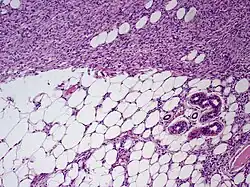

Ważną cechą jest naciekanie sąsiednich tkanek. Naciek tkanki podskórnej jest widoczny w formie zawierających pojedyncze atypowe komórki wypustek przez przegrody oraz zraziki tłuszczowe i przyjmuje formę plastra miodu lub wielowarstwowych pasm komórek wrzecionowatych położonych równolegle do skóry[7]. W zaawansowanych stadiach widoczny jest naciek głębiej położonych struktur[7].